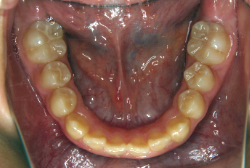

叢生(そうせい)

凸凹な歯並びのことを叢生といいます。矯正歯科に来院する患者様の主訴の中で、最も多いのが「配列の凸凹を真っ直ぐにしたい」というものです。歯の大きさと顎の大きさの調和がとれていないことが原因です。

凸凹を主体としたケースの場合、当院の平均治療期間は18ヶ月ですので、このケースは少し長めに経過しました。理由の一つは凸凹の程度がかなり重症だったと言うことですが、もう一つは、右下第2大臼歯が45度くらい前傾していたため、それを整直化させるために時間を要したと考えています。いずれにしても最終結果は大変よい状態と思います。

治療前は並びが乱れて見た目が悪いというのはもちろん問題ですが、歯科医学的に一番困るのは噛み合わせが悪いという点です。上下の犬歯(3番目の歯)は、上下的に離れた位置にあるため接触することができません。つまり歯としては存在していても、歯としては機能していないということです。